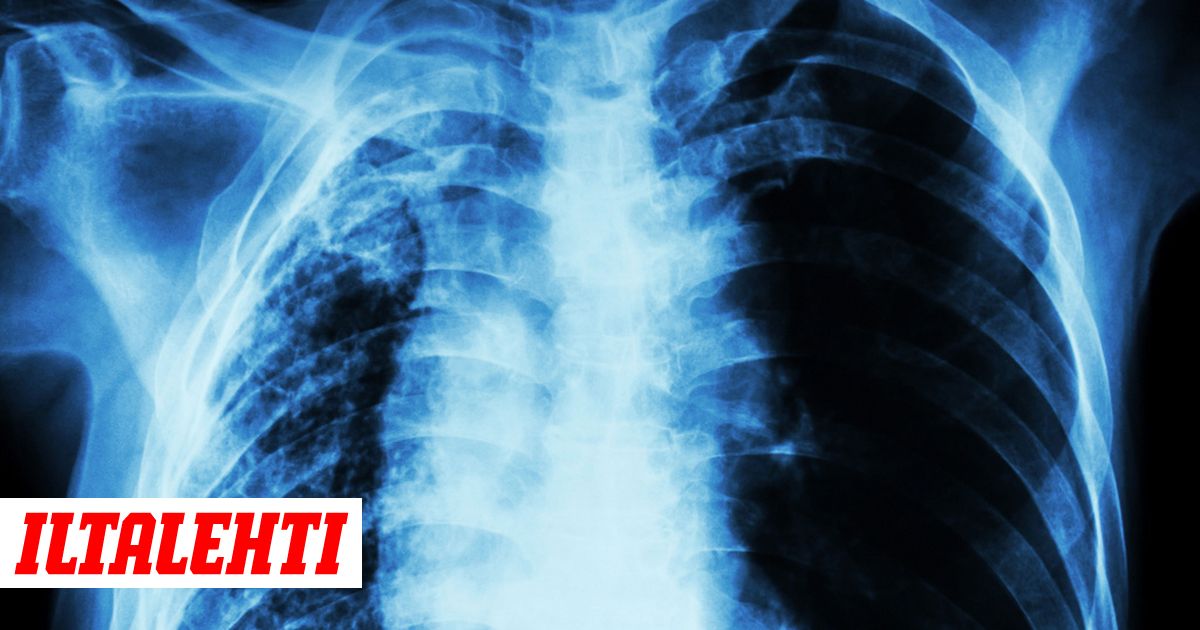

Keuhkokuume altistaa sydämen vajaatoiminnalle Kuumeeton Keuhkokuume Oireet keuhkokuume on keuhkokudoksen infektiota, jonka oireet voivat muun muassa olla kuume, yskä,. Sairauksen oireet ovat yleensä rajumpia ja voivat muistuttaa tavallista flunssaa tai nuhakuumea. Korkeaa kuumetta ja kylkikipuakin voi esiintyä, mutta ei läheskään aina. keuhkokuume on keuhkokudoksen tulehdustauti, joka voi aiheutua kuumetta, yskää, hengityskipua ja vinkuvan hengitystä. Tautia edeltää usein viruksen aiheuttama ylähengitystieinfektio, ja siihen liittyy usein se,. Kuumeeton Keuhkokuume Oireet.